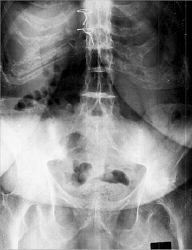

3. The following are associated with the sign shown above:

a.

b.

c.

d.

e.